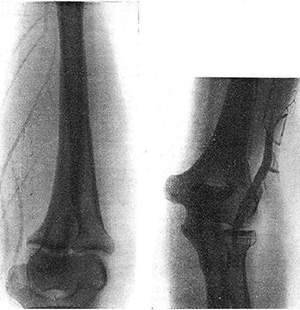

図2. 臭化ストロンチウムによる世界初の生きたヒトの血管造影.

【要旨】末梢血管を撮影するために造影剤を検討し,臭化ストロンチウムが最適であった.10~20%臭化ストロンチウム5~10ccを血管内に注入し中枢側をうっ滞させて,生きた人間の四肢末梢動静脈のX線撮影に成功した.肺血管の撮影には成功していないが,脂溶性造影剤を家兎に注射して,右心系,肺に油滴が移動することを観察できた.今後,臭化ストロンチウムによる肺循環の造影,さらには脊髄,脳室造影も期待できる.

【解説】ヒトにおける血管造影の報告である.造影剤としては,原子番号の大きな元素をいろいろ試した結果,臭化ストロンチウム(SrBr2)を使用している.ストロンチウムは当時,くる病,低カルシウム血症の治療に使われていた.手技の詳細については記載がないが,上肢の中枢側の血流を(おそらく駆血帯により)うっ滞させた状態で動注あるいは静注したものである.決して良い造影とは言えないが,それなりに動静脈が写っており,何はともあれ世界初の血管造影であった(図2). 論文の後半では,この方法をさらに肺循環に発展させる計画について触れ,水溶性造影剤には限界があることから,油性造影剤(リピオドール)について研究を進めていることが触れられている.